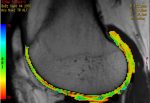

Es un estudio especializado de resonancia magnética donde se aplican secuencias específicas para la valoración del cartílago articular y detectar lesiones iniciales, aun cuando no son visibles en las secuencias convencionales. Esto se logra mediante secuencias que se conocen como mapa T2 o cartigram que consiste en la adquisición de un tren de ecos que permite el estudio del colágeno y la matriz extracelular del cartílago y así detectar lesiones microscópicas, permitiendo el diagnóstico y tratamiento tempranos, permitiendo a su vez realiza estudios de seguimiento para valoración de la respuesta del tratamiento inicial.